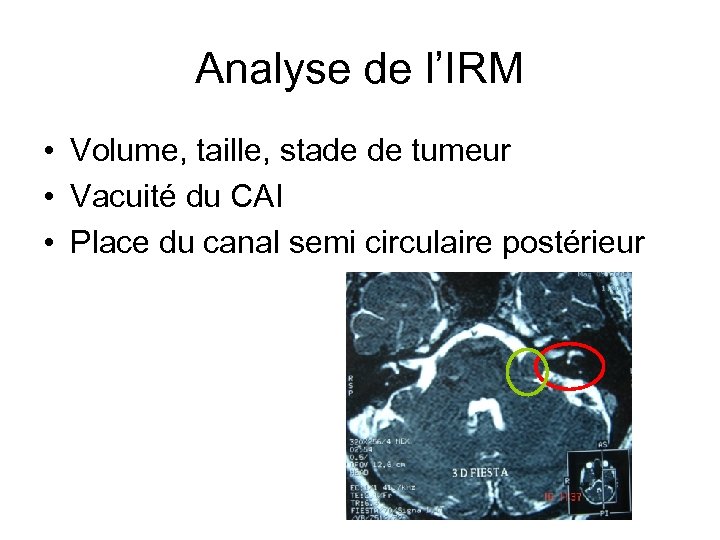

Analyse de l’IRM • Volume, taille, stade de tumeur • Vacuité du CAI • Place du canal semi circulaire postérieur

Analyse de l’IRM • Volume, taille, stade de tumeur • Vacuité du CAI • Place du canal semi circulaire postérieur